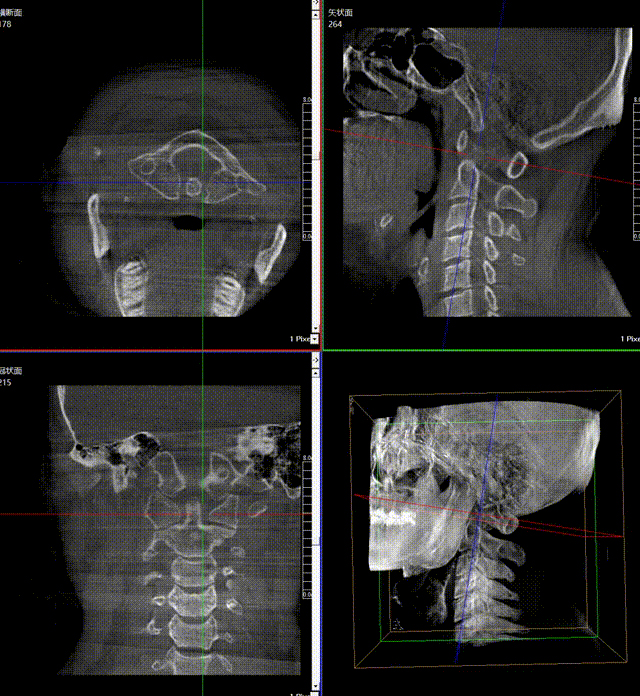

通常上頸椎的手術(shù)是非常復(fù)雜的,因為醫(yī)生要把釘子打在上頸椎這樣一個很狹小的通道里面,周圍都是重要的神經(jīng)血管,一旦損傷到頸椎,就有可能造成病人的死亡。隨著醫(yī)學(xué)影像技術(shù)的不斷發(fā)展,在三維影像的引導(dǎo)下,整個打進(jìn)去的通路能夠完全的展現(xiàn)在我們的眼睛里,讓這種復(fù)雜的手術(shù)變得簡單了,更多的醫(yī)生就可以去開展這樣的手術(shù)了,也會有越來越多的病人從中獲益。